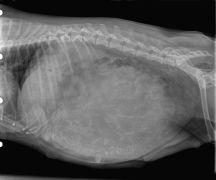

Radio abdominale

Mégaoesophage

Fécalome

radiographie abdominale vétérinairemégaoesophage infini‘Vetfécalome infini‘Vetradiographie dysplasie coxofémorale chien

Nous disposons d'un équipement de radiologie numérique.

Les radiographies sont d'un atout majeur dans le diagnostic de nombreuses pathologies (fractures, problèmes respiratoires, troubles digestifs ...).